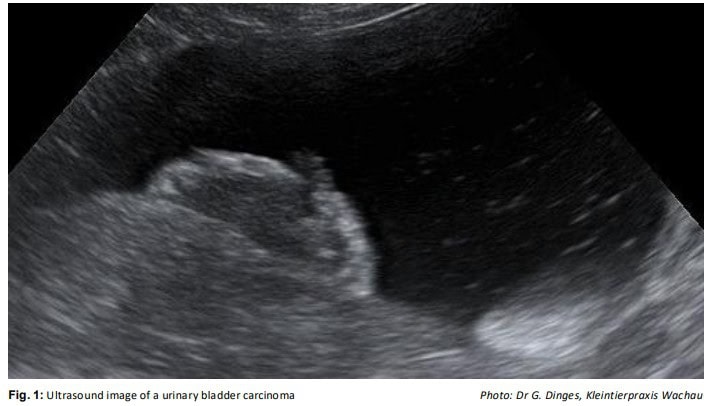

In dogs, both urothelial carcinomas (UCa) of the urinary bladder, as well as urethra and prostate carcinomas (PCa), are highly malignant neoplasms. These are often diagnosed relatively late (e.g. by ultrasound Fig. 1) and have a poor prognosis. By testing for the presence of the V595E mutation in the BRAF gene, diagnosis can be made early, and even with urine sediment. A NEW supplementary test that can be used, if no BRAF mutation has been found, and the sensitivity of the overall examination needs to be increased. At Battlab this combined test is referred to as the BRAF comp/plus test. Both tests are discussed here.